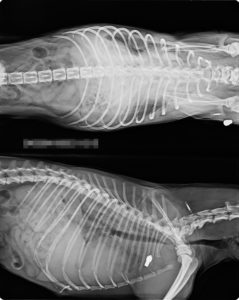

A röntgenfelvételeken jól látszódik, hogy a lőszer a kutya testébe fúródott.